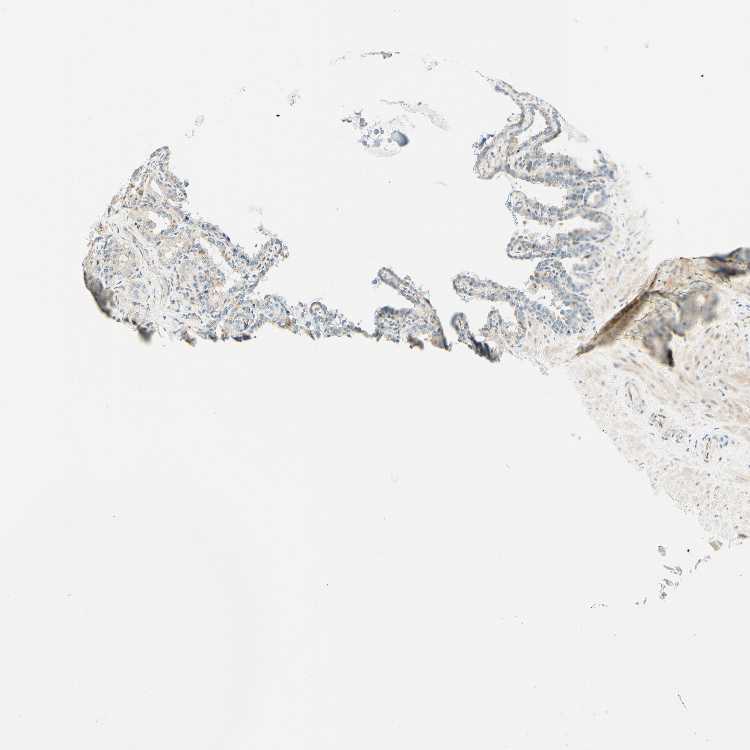

SEMINAL VESICLE - Antibody stainingi

Antibody staining in the annotated cell types in the current human tissue is reported as not detected, low, medium, or high, based on conventional immunohistochemistry profiling in selected tissues. This score is based on the combination of the staining intensity and fraction of stained cells.

Each image is clickable and will lead to virtual microscopy that enables deeper exploration of all samples and also displays staining intensity scores, fraction scores and subcellular localization as well as patient and tissue information for each sample.

Antibody HPA010650

Glandular cells Low